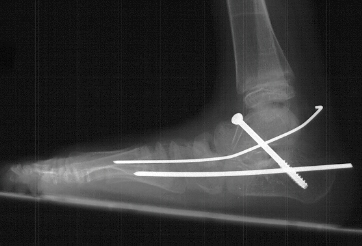

of the left foot. The procedure consisted of :

- subtalar arthrodesis with autograft bone graft and screw fixation

- closing wedge calcaneocuboid arthrodesis with open pinning

- reduction and open pinning of the talonavicular joint

- midfoot soft tissue release of the talonavicular, calcaneocuboid and

subtalar joints

Post operatively, the patient was placed in a long leg cast. Preliminary

results show satisfactory reduction of the talonavicular joint, correction

of hindfoot valgus, dorsiflexion of the talus on the calcaneus, and correction

of forefoot adduction immediately post op.